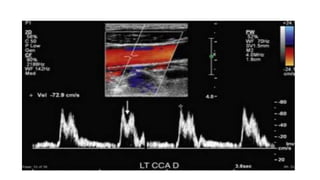

• A high-resistancewaveform pattern with diminished, absent, or reversed diastolic flow is an abnormal finding in the CCA or ICA suggestive of increased peripheral vascular resistance or a distal vascular occlusion or high-grade stenosis. • When PSV is significantly reduced, this appearance has been described as a “knocking” waveform pattern. • Bilateral high-resistance waveform patterns in the ICAs may indicate increased intracranial pressure, diffuse intracerebral vasospasm, or arteritis

• #37 A, Longitudinal color Doppler image reveals that the left proximal CCA (arrows) is occluded. B, PSV is elevated in the mid right CCA (129 cm/sec) and was even more elevated proximally (160 cm/sec; not shown). C, PSV is 269 cm/sec in the right ICA. By SRU criteria, this corresponds to a stenosis of more than 70%. However, on color Doppler imaging (D), there is only a small amount of plaque noted (arrow) in the right ICA consistent with a stenosis of less than 50%. Furthermore, PSVR is approximately 2 : 1, which corresponds to a stenosis of only 50%. PSV is artificially elevated in the right CCA and ICA because of the occlusion of the left CCA.